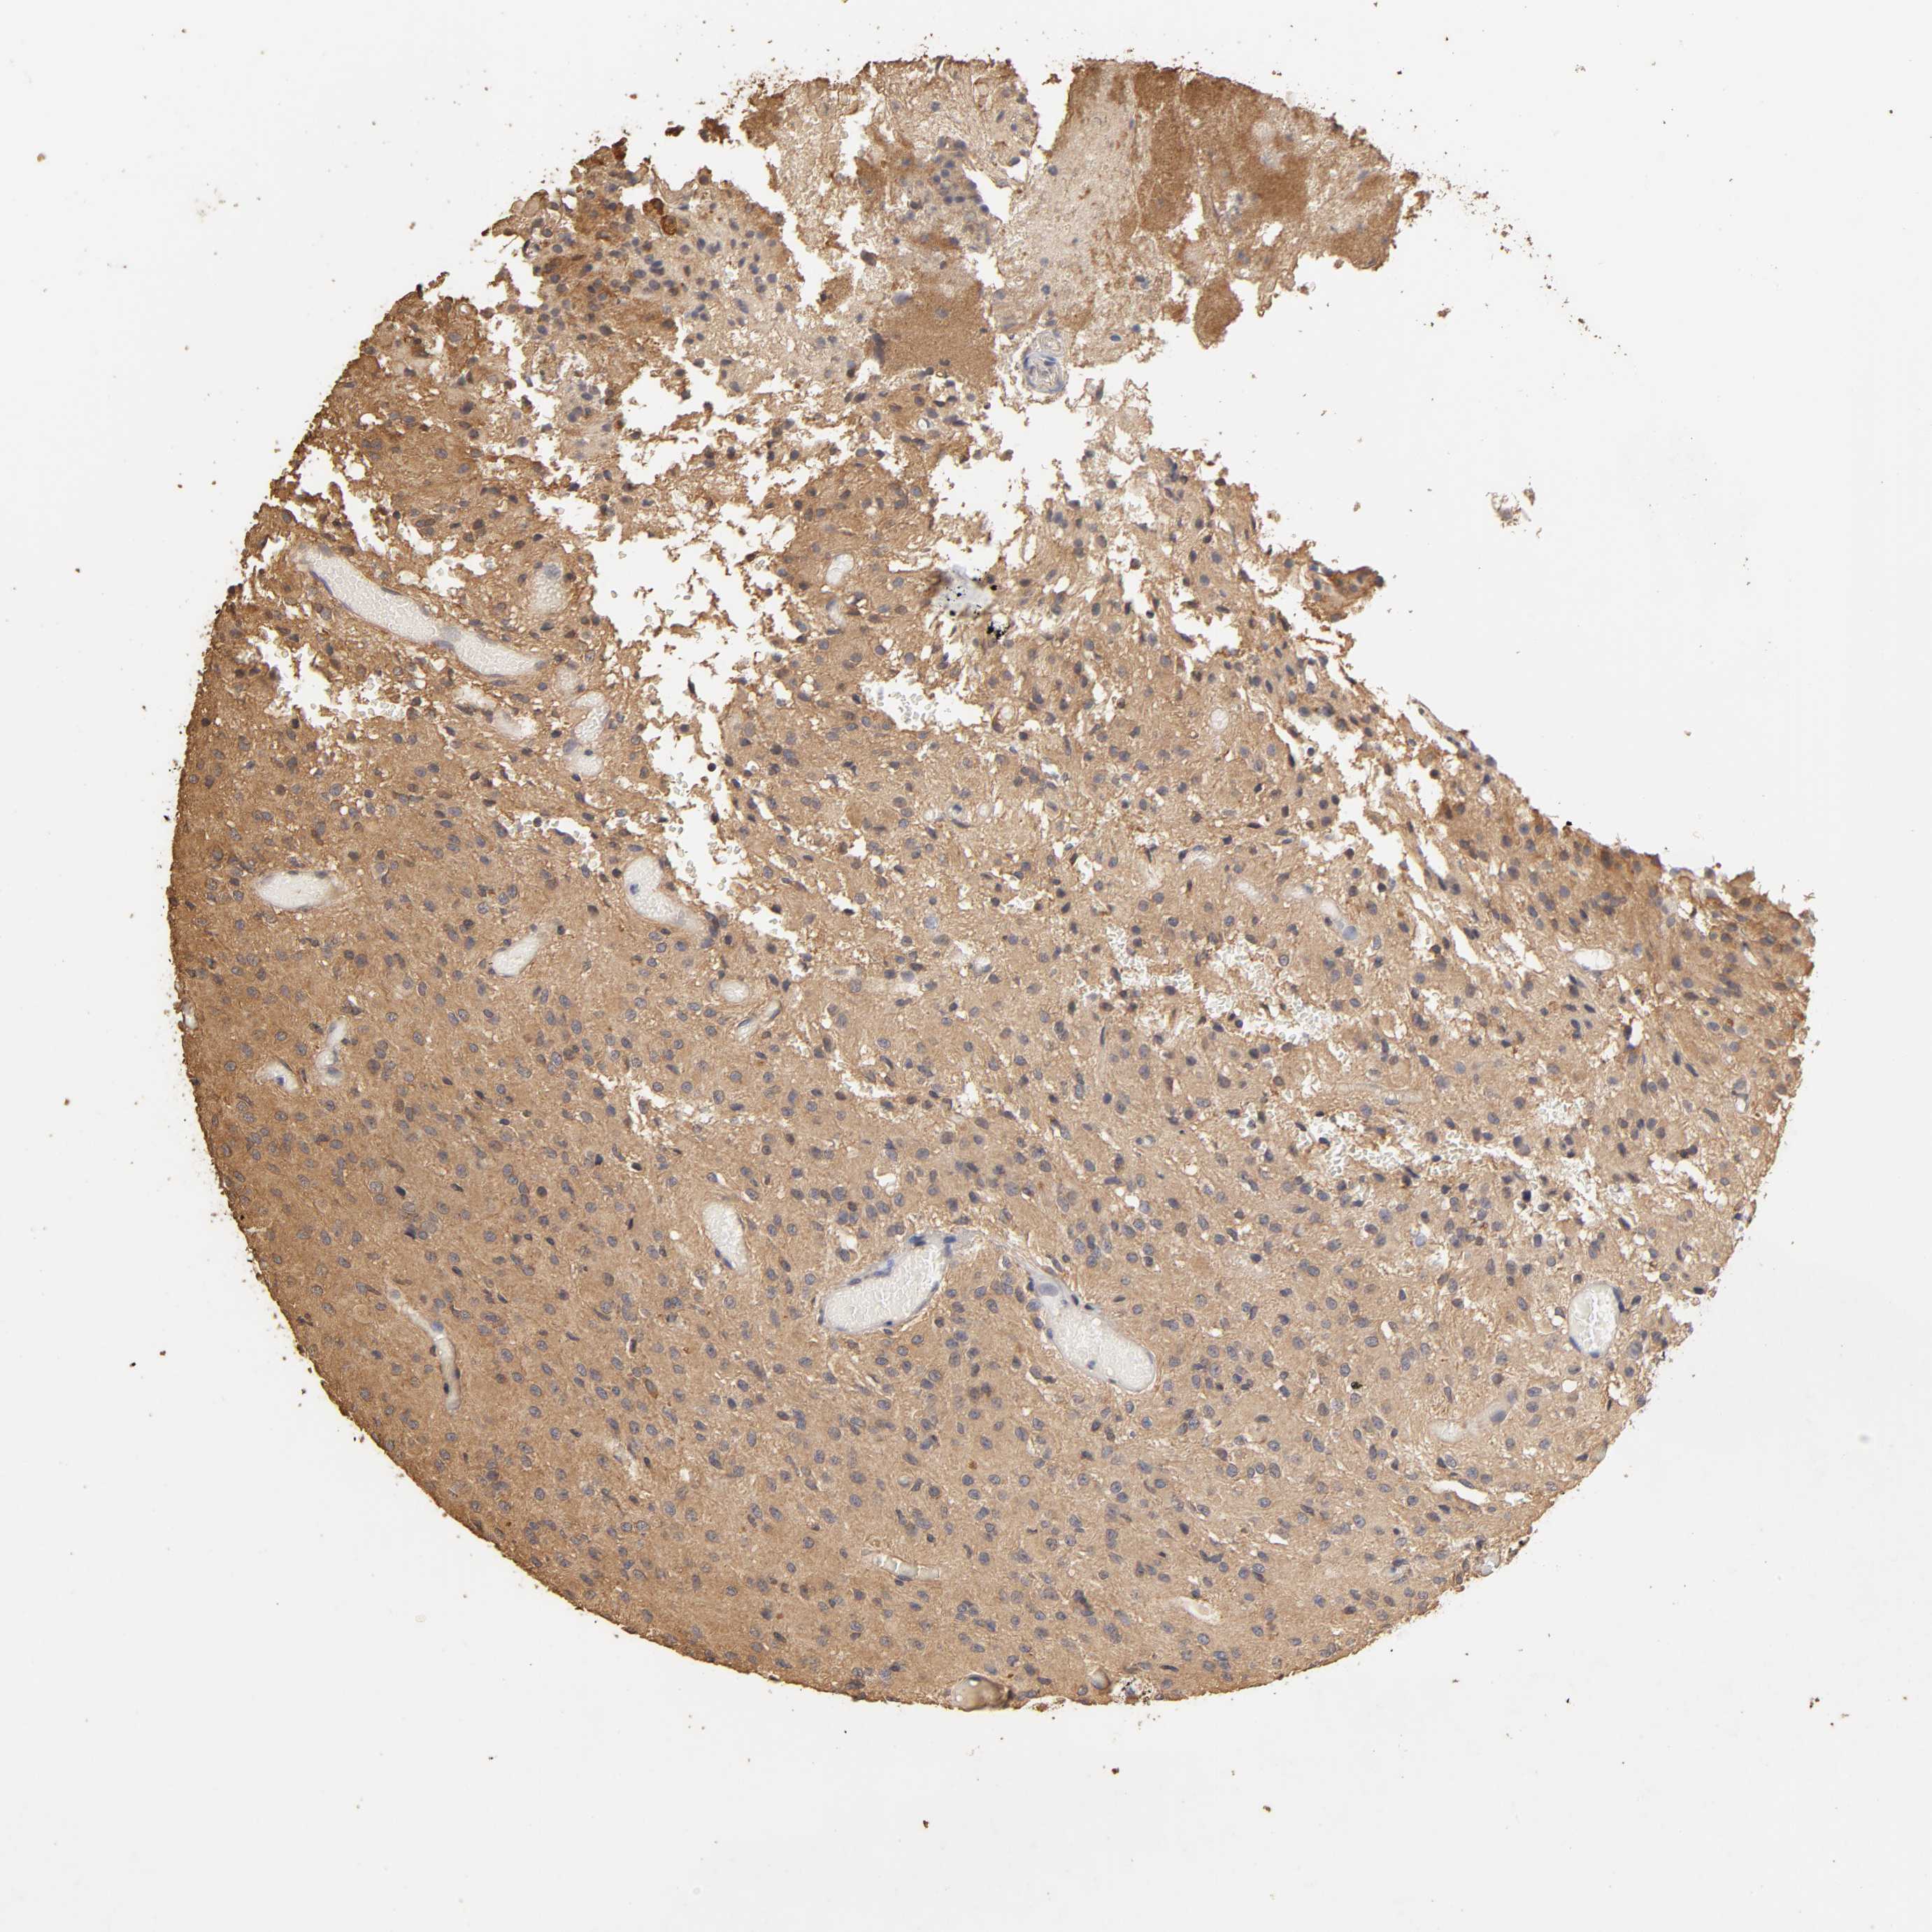

GLIOMA - Protein expressioni

A mouse-over function shows sample information and annotation data. Click on an image to view it in a full screen mode. Samples can be filtered based on level of antibody staining by selecting one or several of the following categories: high, medium, low and not detected. The assay and annotation is described here.

Note that samples used for immunohistochemistry by the Human Protein Atlas do not correspond to samples in the TCGA dataset.

Antibody stainingi

Antibody staining in the annotated cell types in the current human tissue is reported as not detected, low, medium, or high, based on conventional immunohistochemistry profiling in selected tissues. This score is based on the combination of the staining intensity and fraction of stained cells.

Each image is clickable and will lead to virtual microscopy that enables deeper exploration of all samples and also displays staining intensity scores, fraction scores and subcellular localization as well as patient and tissue information for each sample.

Antibody HPA003903

Antibody HPA072756

Antibody CAB026000

Staining

High

Medium

Low

Not detected

Intensity

Strong

Moderate

Weak

Negative

Quantity

>75%

75%-25%

<25%

None

Location

Nuclear

Cytoplasmic/membranous

Cytoplasmic/membranous,nuclear

Glioma, malignant, High grade

Glioma, malignant, NOS

Glioma, malignant, Low grade